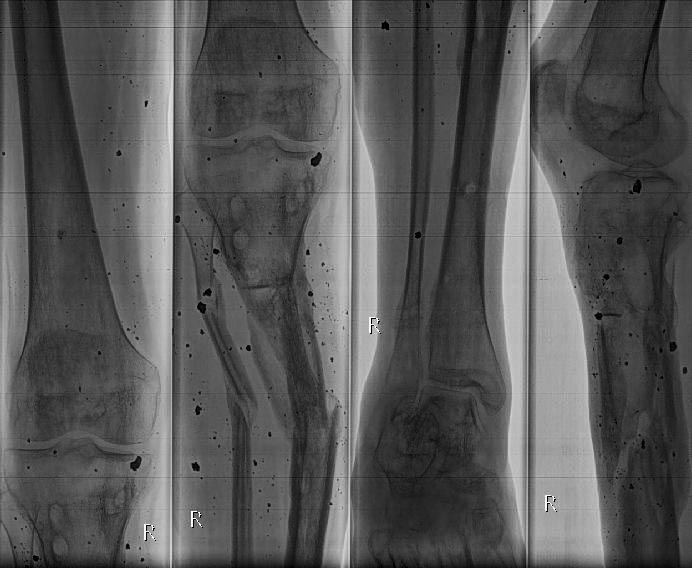

Как лучше устранить деформацию обеих голеней. Уважаемые коллеги на лечение спустя 10 мес. после травмы поступил 35 летний пациент. Изначально лечился в аппаратах. Длительно, в выписке описываются инфекционные осложнения. В настоящее время аппараты демонтированы, ран на правой и левой голени нет. Слева планируем устранить в один прием с фиксацией стержнем. Справа - мнения разошлись: от тоже стержнем, до остеотомии в нижней трети (вне перелома) с коррекцией механической оси. Прошу поделиться мнениями и опытом. Спасибо!

Извините, но слишком мало информации - когда сняли аппараты, почему, каков объём движений в суставах, как передвигается пациент, когда было купировано воспаление и каков характер оно имело, каково кровообращение, иннервация, состояние мягких тканей. Дать совет только по снимкам невозможно.

Стоило бы поподробнее представить свой план коррекции, скиаграммы, и потом задавать более конкретные вопросы.

Как именно на левой голени планируете коррекцию? Где чего пересекать-разъединять?